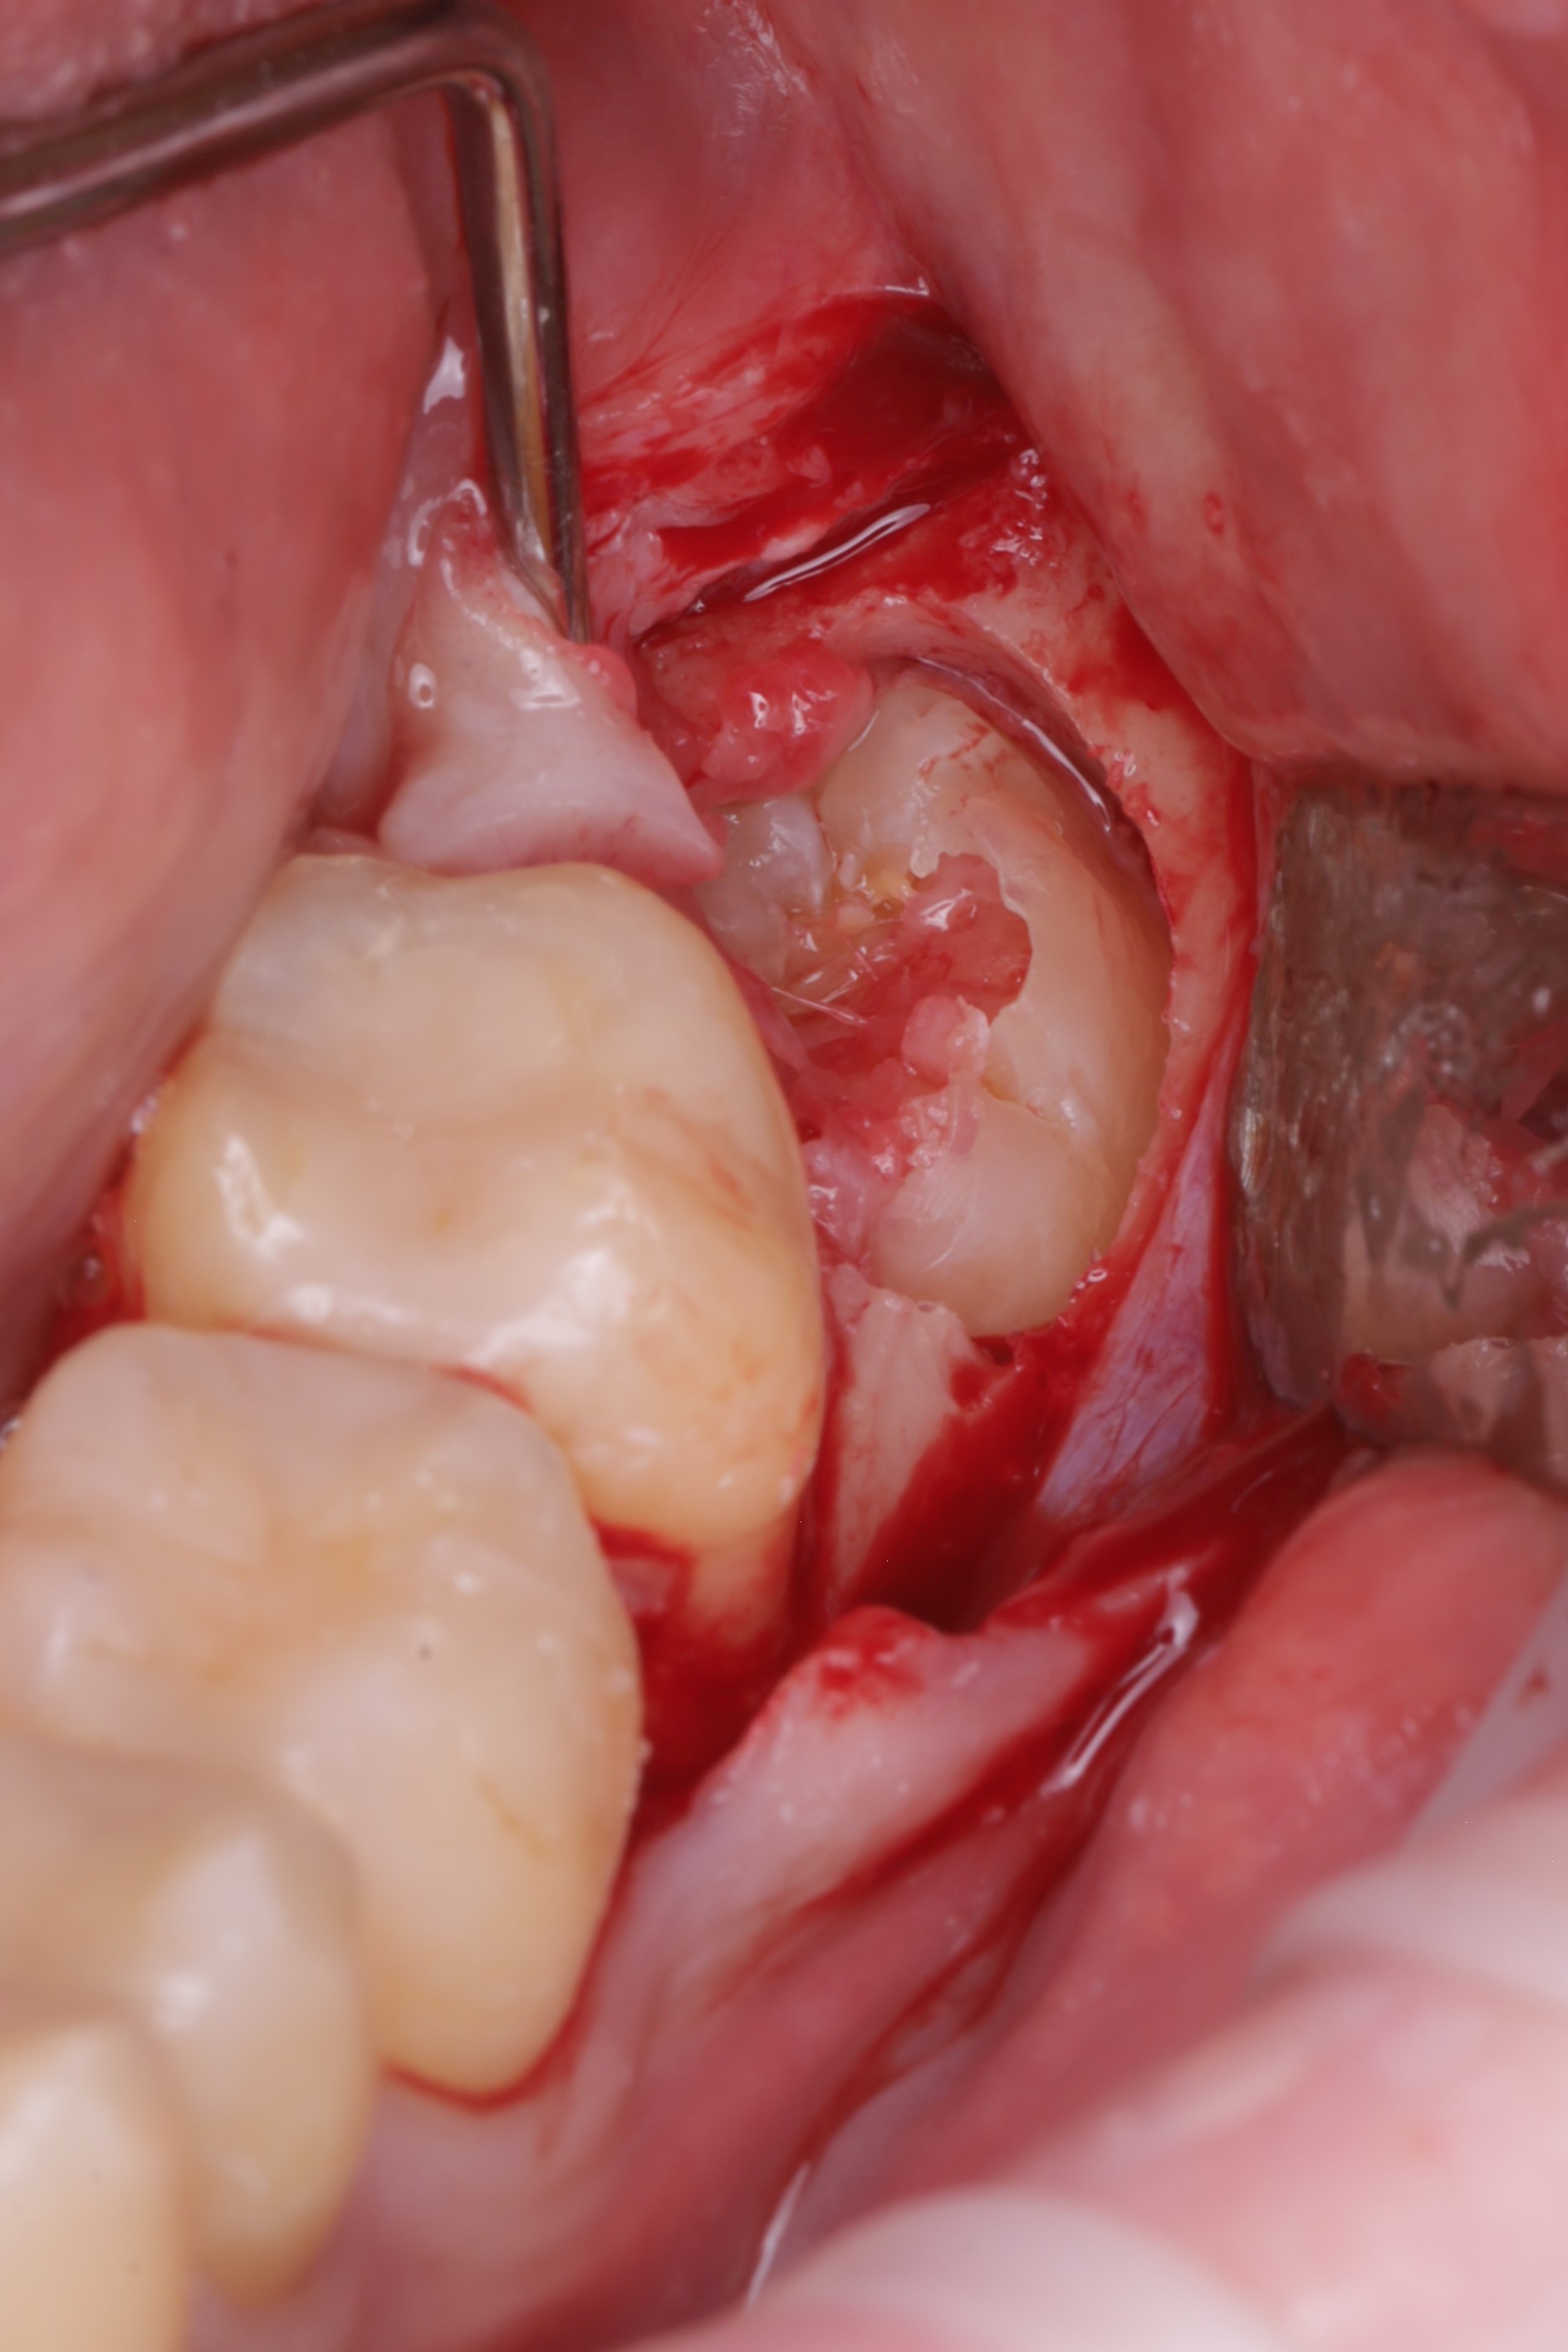

Аккуратно сформирован доступ к ретинированному зубу

Произведено иссечение тканей коронковой части зуба